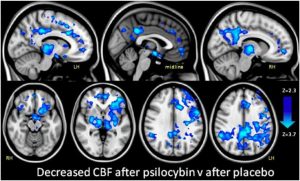

Psychedelic mushrooms have been used for medical, ceremonial and spiritual purposes for thousands of years, due their mind-alterating properties which induce hallucinations, perception disorders or altered states of awareness. It’s been found that the active ingredient responsible for the psychedelic state, which many associated with a religious experience, is a substance called psilocybin. Though a lot is […]